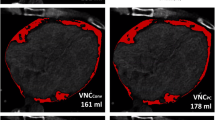

The measurements shown in Fig. 2 demonstrate the effect of increasing tube voltage on PCATMA values. For both 256-slice CT scanner and dual-source CT system, the applied tube voltage led to a statistically significant difference in PCATMA (tube voltage effect: p < 0.001 for 256-slice CT and p = 0.013 for dual-source CT). The highest PCATMA values were measured at 140 kVp and the lowest ones at 80 kVp. Additionally, a significant difference in PCATMA values was observed between IR and FBP reconstructed images for both 256-slice CT (group effect, p < 0.001) and dual-source CT (group effect, p = 0.014) scanners. In particular, for both manufacturers, the use of IR resulted in a higher PCATMA as compared to FBP. No significant difference was found between the two manufacturers for measurements based on the same type of reconstruction.

Effect of kVp and image reconstruction on PCATMA in porcine hearts. For both CT manufacturers, PCATMA increased with increasing values of tube voltages. The implementation of IR resulted in higher values of PCATMA as compared to FBP for each value of tube voltage. The yellow background indicates the HU range corresponding to adipose tissue. Means and standard errors are reported. Abbreviations: CT, computed tomography; FBP, filtered back projection; HU, Hounsfield unit; IR, iterative reconstruction; kVp, kilovoltage peak; PCATMA, pericoronary adipose tissue mean attenuation